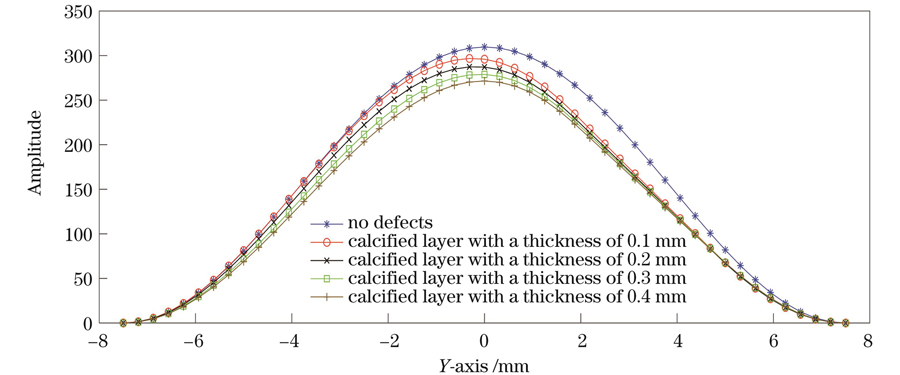

First, the theoretical analysis proves that using the spatial carrier phase extraction method to detect the amplitude distribution in eardrum samples in the vibration mode is reasonable. In the finite element simulation and experimental analysis, the vibration modes of the artificial eardrums with defects were analyzed, and the results showed that different defects affect the amplitude distribution in the first-order vibration mode for the eardrums differently. For the perforated eardrum samples, the amplitude distribution was analyzed by varying the size and location of the perforation. The results show that the amplitude near the perforation increases significantly with the increase in perforation size (Figs. 3 and 4), and an increase in the number of fringes is observed in the experimental results (Fig. 11). By changing the location of the perforation, the maximum amplitude shifts off-center with the perforation, and the larger the perforation, the more evident the deviation. The amplitude distribution for the scratched eardrum samples was analyzed by varying the size and location of the scratch. The results show that at the same location, the larger the scratch length, the larger the surface amplitude of the film (Fig. 5), and the amplitude changes more significantly near the scratch location (Fig. 6). The experimental results show an increase in the number of fringes, and the shape of the fringe near the central scratch is flat (Fig. 12). When the scratch is off-center, the effect on the amplitude near the scratch is significantly greater than that at the center. The amplitude distribution for the calcified eardrum samples was analyzed by varying the thickness of the calcified layer (Fig. 7). The amplitude of the film decreases with an increase in the thickness of the calcified layer but is more evident at the location of the calcified layer (Figs. 8 and 13).

耳膜钙化常常是由耳部炎症引起的,表现为耳膜表面白色斑块状钙盐沉积,钙化严重的情况下会导致听力下降。如

图 7. 钙化薄膜一阶振动模态的仿真结果。(a)钙化薄膜示意图;(b)~(e)钙化厚度为0.1、0.2、0.3、0.4 mm的薄膜

Fig. 7. Simulation results of first-order vibration modes of calcified films. (a) Schematic of calcified film; (b)-(e) films with calcification thickness of 0.1, 0.2, 0.3 and 0.4 mm, respectively

在钙化薄膜的实验验证中,为了模拟真实的耳膜钙化情况,在薄膜表面涂抹不同厚度的尺寸为3 mm×3 mm的钙化材料。分别在相同位置处涂抹0.1 mm和0.3 mm厚度的钙化材料,如

图 13. 钙化薄膜的一阶振动模态图。(a)钙化厚度为0.1 mm的薄膜;(b)钙化厚度为0.3 mm的薄膜

Fig. 13. First-order vibrational mode diagrams of calcified films. (a) Film with calcification thickness of 0.1 mm; (b) film with calcification thickness of 0.3 mm